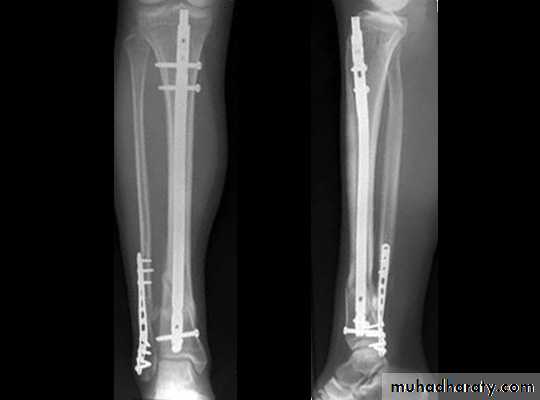

INTERNAL FIXATION

Indications

advantages

EXTERNAL FIXATIONPrinciple

IndicationsAdvantages